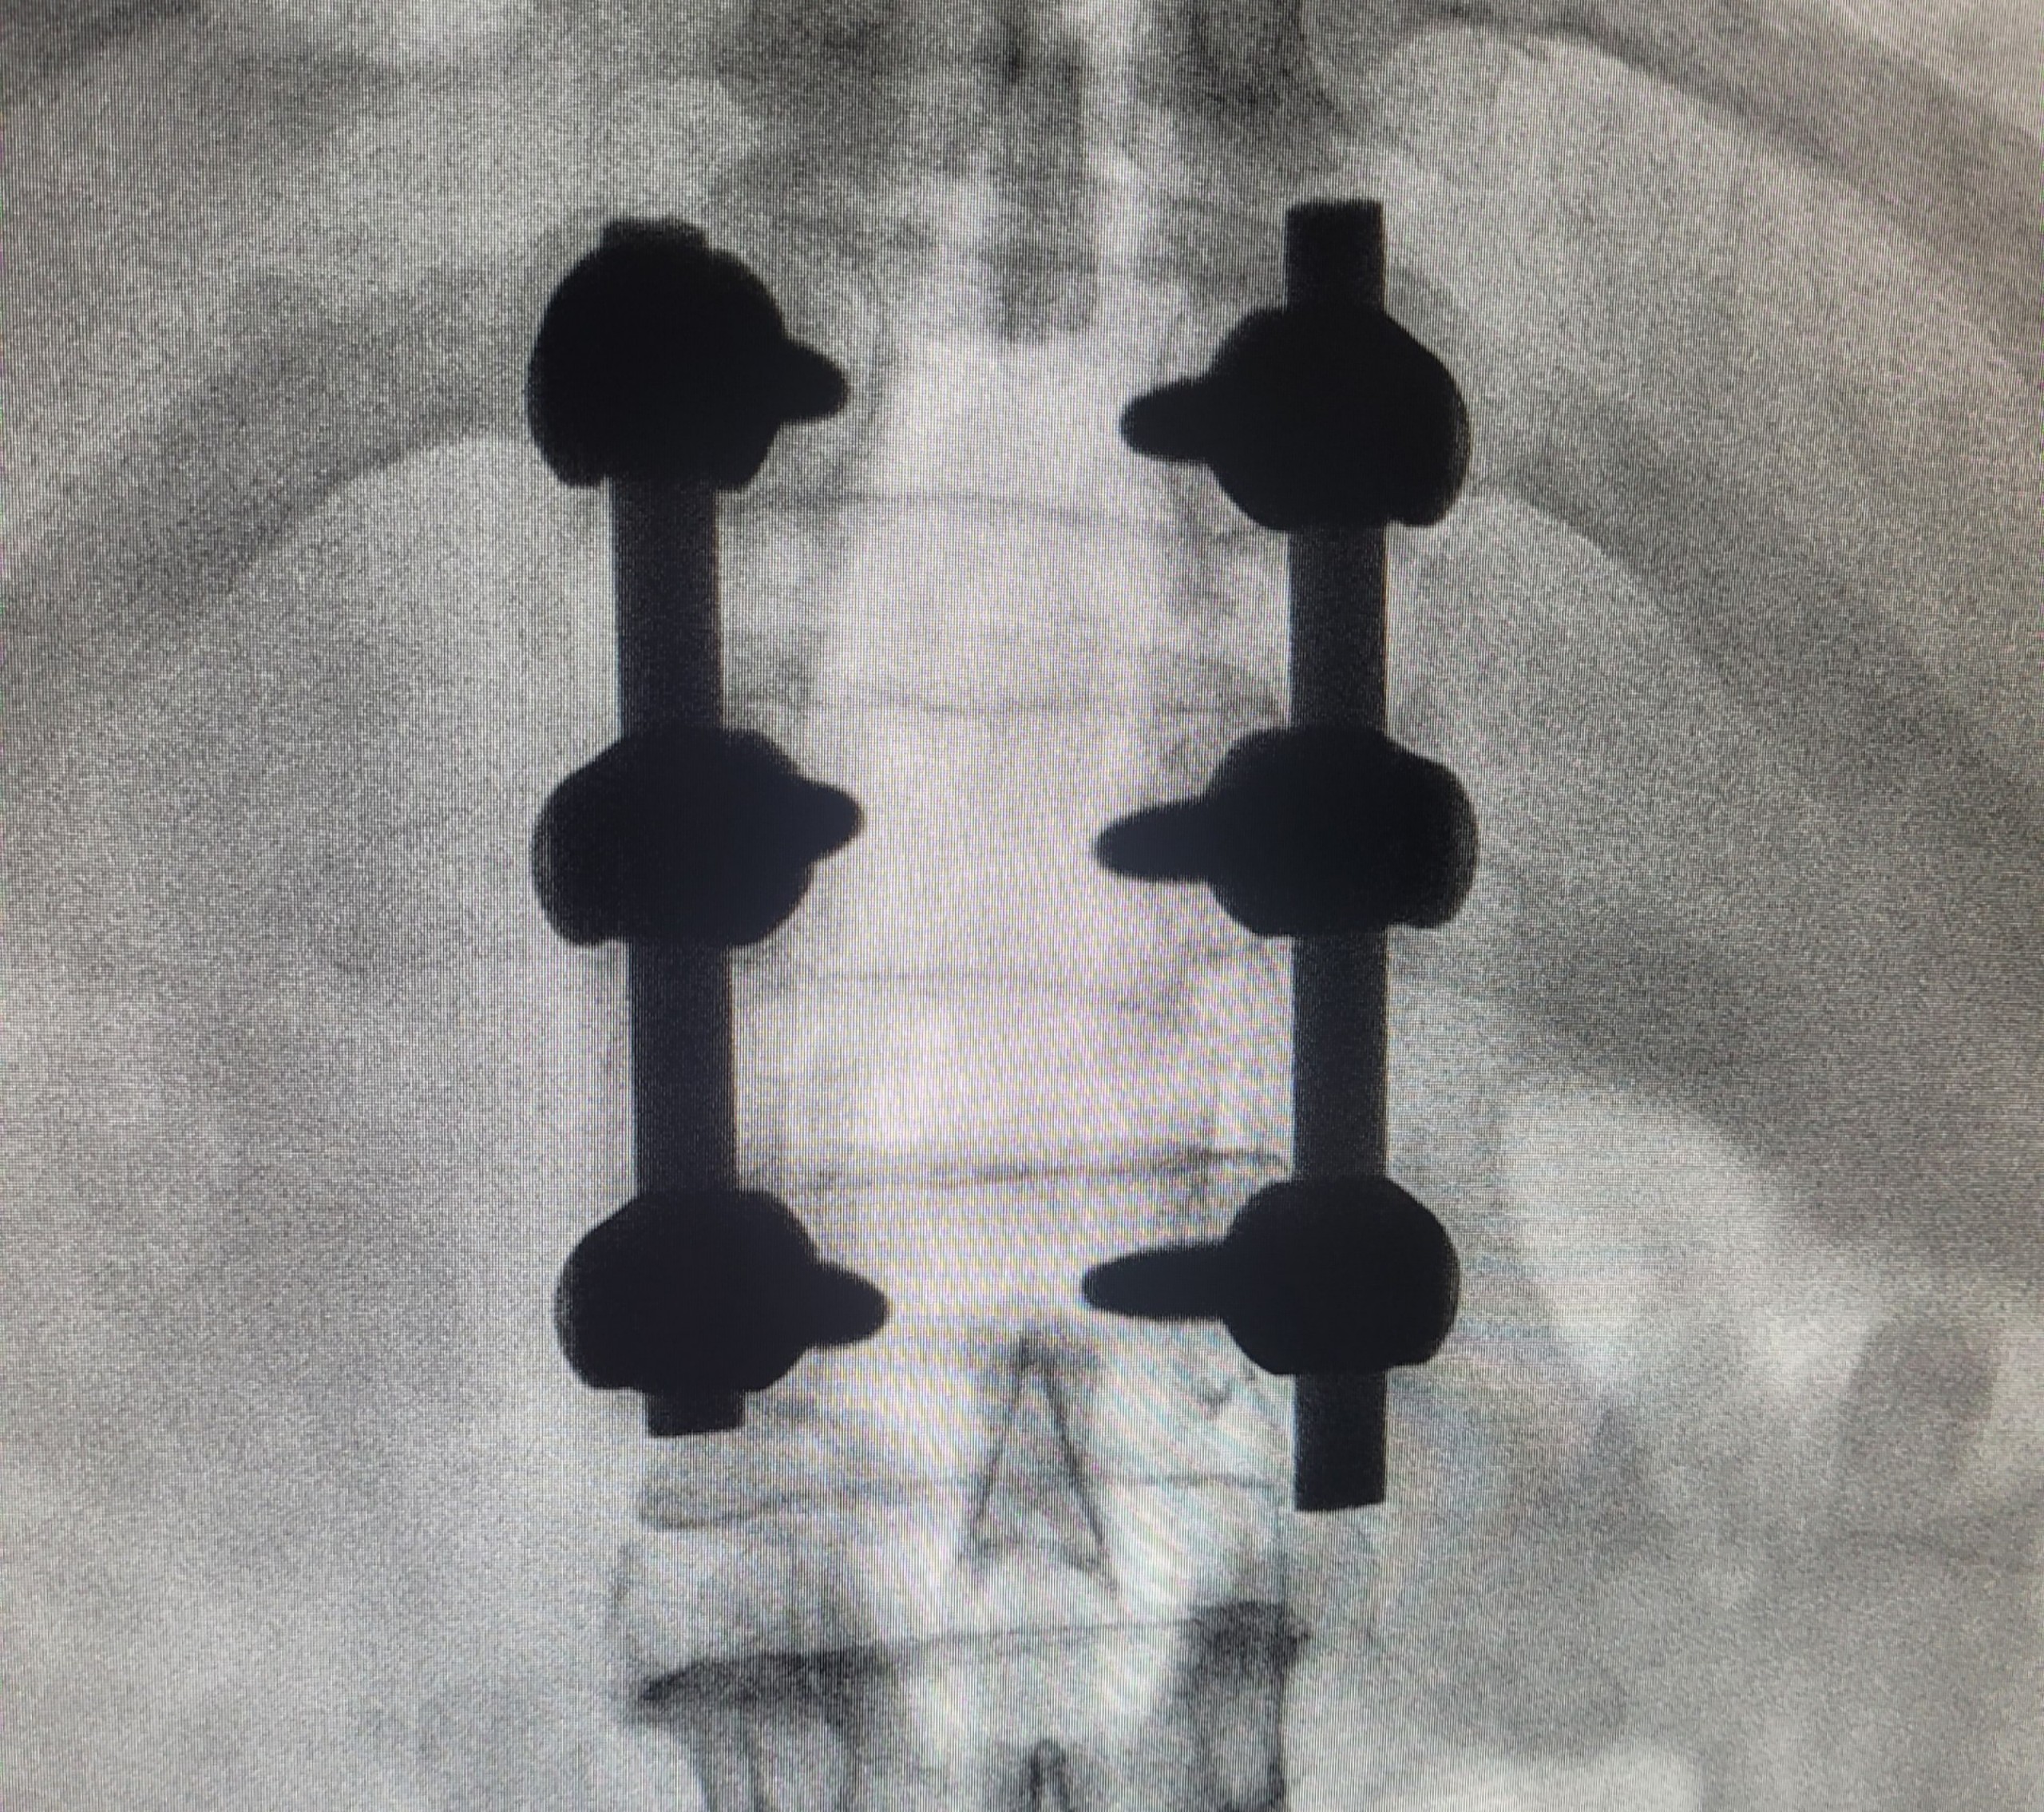

BSCKII. Trần Kim Hà – Phó trưởng khoa Phẫu thuật thần kinh lồng ngực cho biết: “Do vùng cột sống có cấu trúc giải phẫu phức tạp, khối u chèn ép, dính vào các dây thần kinh, đòi hỏi phẫu thuật viên phải khéo léo, cẩn thận để bóc tách, bộc lộ khối u, hạn chế tổn thương tủy. Để bảo vệ an toàn cấu trúc tủy sống và rễ thần kinh bệnh nhân.đã được cố định cột sống bằng nẹp vít”

Hình ảnh cột sống được cố định bằng nẹp vít